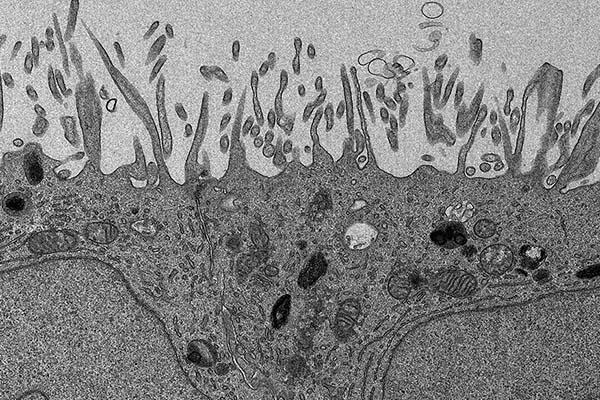

image: An electron microscopy image of human retinal cells, which were analyzed in a new study on a rare eye disease known as MacTel. The cells were created using induced pluripotent stem cell technology.

The scientists then used human induced pluripotent stem cells to generate specialized retinal cells that contained one of the MacTel-associated PHGDH mutations. They found that a PHGDH mutation in these cells leads to the production of a toxic lipid previously shown to cause MacTel.